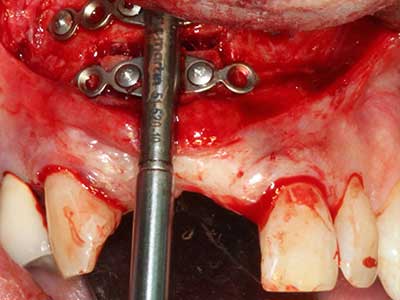

Sollen chirurgische Eingriffe mit unmittelbarer Knochenbeziehung an empfindlichen Strukturen wie Blutgefäßen oder Nerven erfolgen, so bergen rotierende Instrumente ein erhebliches Potential an iatrogener Schädigung. Gerade bei Nervdarstellungen nach iatrogener Schädigung, oder aber im Zuge einer Nervlateralisation für resektive und rekonstruktive Eingriffe oder Implantatinsertionen können piezoelektronische Geräte hilfreich sein Knochendeckel zu präparieren und nervnahe Hartgewebsanteile zu entfernen (Abb. 17-20). Ein leichter Kontakt des Nervstrangs zur Piezospitze bleibt dabei in der Regel folgenlos – allerdings kann eine unvorsichtige Vorgehensweise mit sägeartigen Bewegungen bzw. Ansätzen bei noch vorhandener knöcherner Unterlage durchaus temporäre oder aber auch permanente Nervschädigungen verursachen. Das Risiko einer solchen Schädigung wird jedoch als wesentliche geringer eingeschätzt als unter Anwendung von Säge- oder Fräsinstrumenten (Pereira, Gealh et al. 2014).